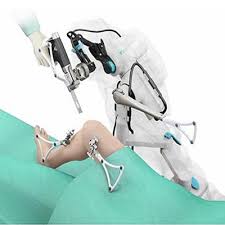

Introduction Robotic hip replacement in Rajnandgaon is transforming the way …

Introduction Robotic knee replacement in Rajnandgaon is redefining the treatment …

Introduction Robotic orthopedic surgery in Raipur is rapidly transforming how …

Introduction Robotic knee replacement in Raipur is an advanced orthopedic …

Introduction Robotic joint replacement in Raipur represents the latest advancement …

Introduction Robotic knee replacement in Raigarh is an advanced orthopedic …

Introduction Robotic joint replacement in Raigarh is transforming orthopedic care …

Introduction Robotic knee replacement in Narayanpur is an advanced surgical …

Introduction Robotic joint replacement in Narayanpur is an advanced orthopedic …